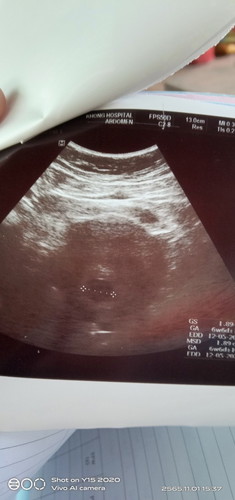

เราพอทราบว่าตั้งครรภ์ก็ไปฝากทันทีตั้งแต่เดือนแรก พอนัดที่2หมอซาวด์ให้เจอถุงตั้วครรภ์แต่ยังไม่เจอตัวอ่อนตอน6w+6 แล้วพอ13wหมอนัดอีกครั้งวันนั้นมีกลืนน้ำตาล100gเจาะ4ครั้ง ผลไม่เป็นเบาหวานขณะตั้งครรภ์ระหว่างรอผลเลือดปวดฉี่ไปเข้าห้องน้ำเอาทิชชู่ซับเจอเลือดปนมูกคุณหมอเลยซาวด์ให้ผลเจอแต่ถุงตั้งครรภ์เหมือนเดิม หมอตรวจภายในบอกมีเลือดนิดหน่อย หมอเขียนใบส่งตัวไปรพ.ใหญ่ในจังหวัด ในใจลึกๆก็เสียใจ แต่ไม่เป็นไรดีกว่าน้องเกิดมาแล้วไม่สมบูรณ์ค่ะ พี่2คนเกิดมาไม่เคยมีปัญหาอะไรแบบนี้เลย แต่มีความรู้สึกว่าตัวเองเหมือนคนไม่ท้องคุยกับแฟนบ่อยว่าตัวเองไม่รู้สึกถึงการตั้งครรภ์เลยท้องนี้ เป็นกำลังใจให้ทุกคนที่เจอเครสแบบนี้นะค่ะ